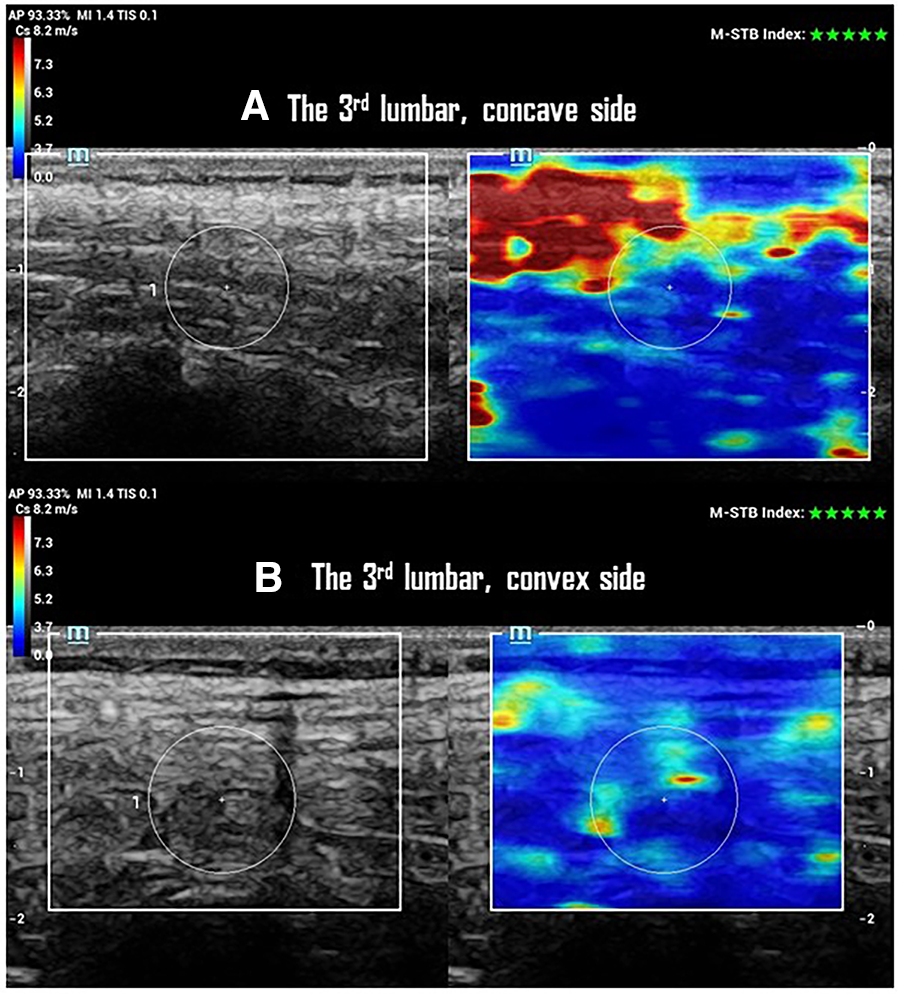

A higher SWS on the concave side with no change of CST was observed at AV of the major curve in the progressive case (Figure 2). This resulted in a smaller SWS-ratio (repeated measurements: 0.8 ± 0.2, 0.9 ± 0.3, 0.9 ± 0.2) at the AV of the multifidus (p < 0.01), longissimus (p < 0.01), and iliocostalis (p = 0.04) muscles in the progression group (Table 2). However, these findings were not observed at the UEV or LEV in either progression or non-progression groups. The CST and CST-ratio did not differ between the progression and non-progression groups at AV, UEV, or LEV (Table 2). The CST showed no differences between scoliosis and non-scoliosis controls.

Figure 2

SWS and CTS of paraspinal multifidus at the 3rd lumbar vertebrae of one participant with a 25° left lumbar scoliosis in the progression group. (A) Ultrasonographic imaging shows a 10 mm CTS with 4.4 ± 1.4 m/s of SWS in multifidus on the concave side of the curve. (B) Ultrasonographic imaging shows a 10 mm of CTS with 3.9 ± 1.0 m/s of SWS in multifidus on the convex side of the curve.

The data acquired in this study addressed our second research question, revealing that curve progression in mild to moderate scoliosis is associated with distinct changes in the elasticity of PSM. This association was observed with greater AR of the major curve, independent of the curve pattern and SD/KT/LL. However, no such relationship was detected in the CST of PSM. Moreover, no difference in CST of PSM was found between the non-scoliosis and AIS groups in this study cohort (Table 2). Overall, the multifidus, longissimus, and iliocostalis muscles on the concave side of the major curve exhibited greater stiffness (a higher SWS) without a change in thickness in participants with mild to moderate progressive AIS (Figure 2). This change may lead to a discrepancy in PSM elasticity, potentially affecting muscle contractile function.